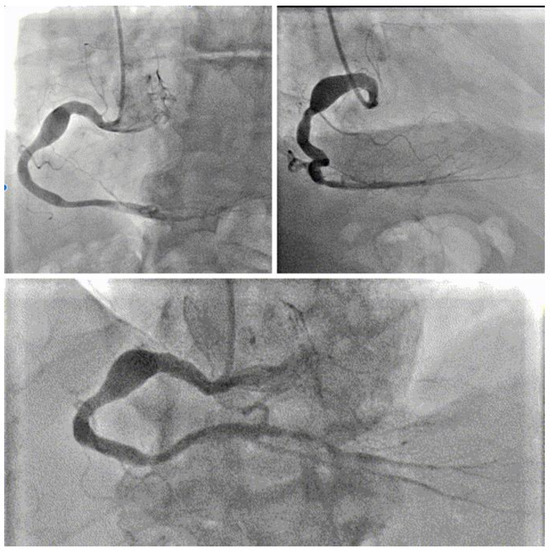

2.2. Examinations

2.3. Management